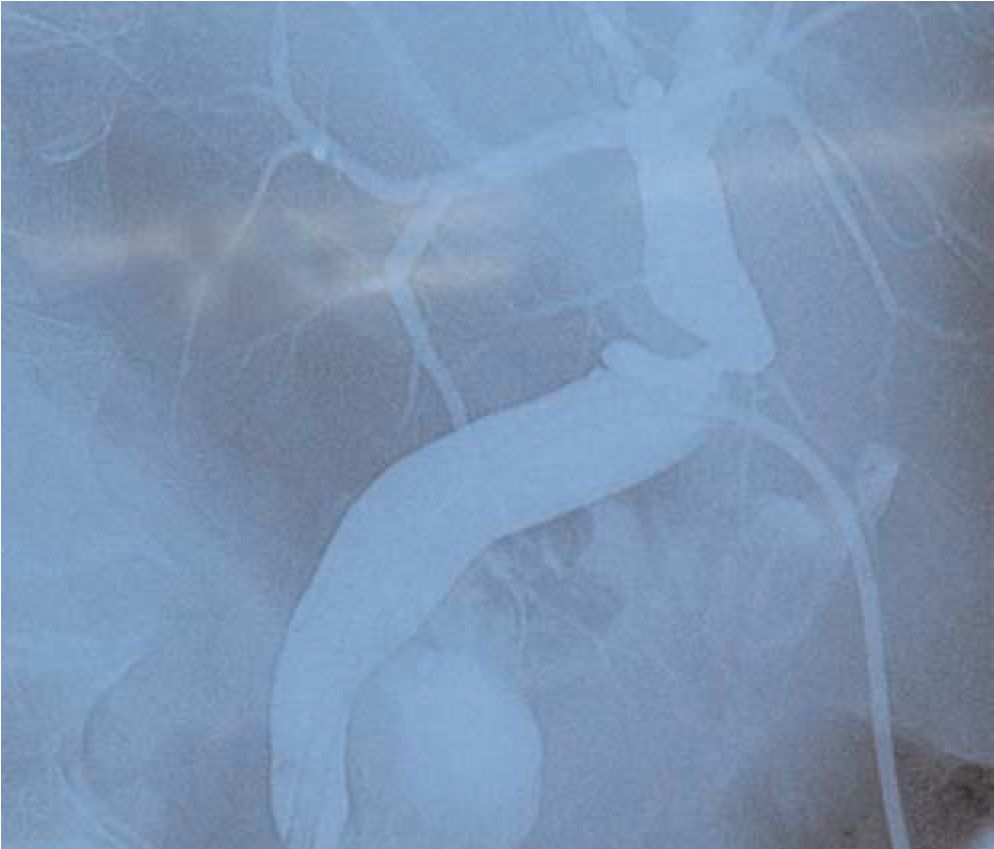

Кроме того, они могут приводить к развитию желчных свищей, перитонита или механической желтухи, а также стриктур желчных протоков (рис. 1-3).

Рис. 1. Стриктура общего печеночного протока после ЛХЭ.

Рис. 2. Клипированный и пересеченный правый долевой желчный проток при ЛХЭ.

Рис. 3. Клипированный правый долевой желчный проток при ЛХЭ.